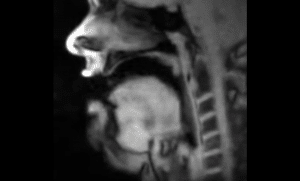

Il video che mostra come si muove la nostra lingua mentre parliamo

È stato pubblicato un video che mostra il funzionamento della lingua umana mentre una persona parla.

È stato realizzato dal fisico e pioniere della risonanza magnetica Jens Frahm per conto della Max Planck Societycompagnia con sede in Germania, a Gottinga.

Nel video si vede la bocca di un uomo dall’interno mentre sta parlando.

La tecnica utilizzata da Frahm velocizza il processo di acquisizione delle immagini ottenute da una risonanza magnetica.

Le immagini assai dettagliate sono state realizzate grazie alla ricerca sulla tomografia a risonanza magnetica (MRT).

Ecco il video che mostra l’interno della bocca di un uomo mentre parla e i movimenti della sua lingua: